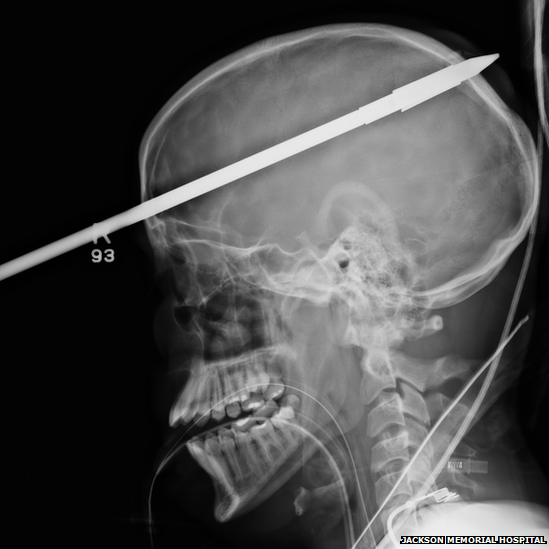

Medics at Jackson Memorial Hospital in Miami said the 3 ft (90 cm) projectile entered his brain over his right eye and went out the back of his head.

After sedating the teenager, part of the stainless steel spear had to be severed with a mechanical cutter so he could fit into the CT scanner.

Also helpful, doctors say, was the foreign object’s trajectory into the right side of the brain, Yasser Lopez’s non-dominant lobe, missing the parts responsible for speech and other important functions.